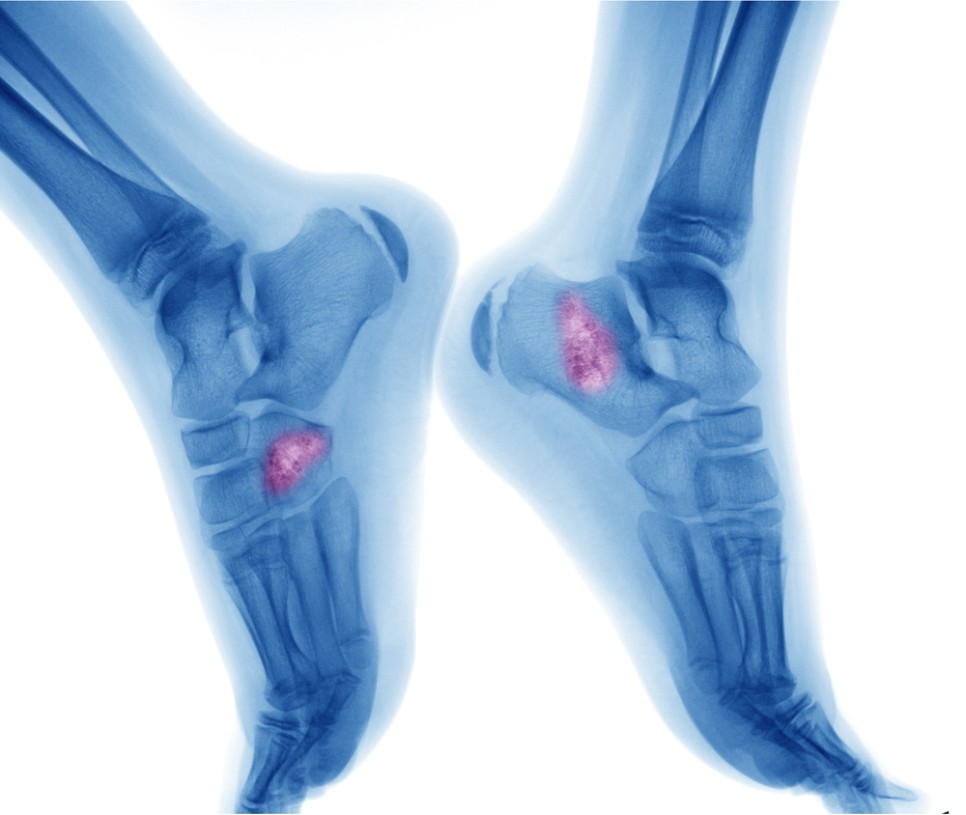

골암의 증상으로는 손발, 무릎의 통증이나 붓기, 부종, 시간이 지날수록 통증이 강해지고 진통제를 먹어도 낫지 않는 등의 증상이 있습니다.

문제는 이러한 골암증상을 단순히 성장통으로 오인하고 빠른 치료시기를 놓칠 가능성이 있다는 점입니다. 골육종은 인체 뼈의 어느 부위에나 발생할 수 있는데 무릎 통증, 골반 통증이 가장 빈번하게 발생하며 이로 인해 무릎 부위가 암에 가장 많이 발생합니다. 성장기 청소년들은 보통 많은 운동을 하고 활동적이어서 이렇게 무릎 통증이나 손발 통증, 부종 등이 나타나더라도 크게 신경 쓰지 않습니다.

골암은 어느 부위에 발병하느냐에 따라 완치율과 예후가 달라집니다. 손발에 생긴 경우는 골반이나 척추뼈보다 더 빠르게 발견할 수 있기 때문에 완치율과 예휴가 더욱 좋습니다.